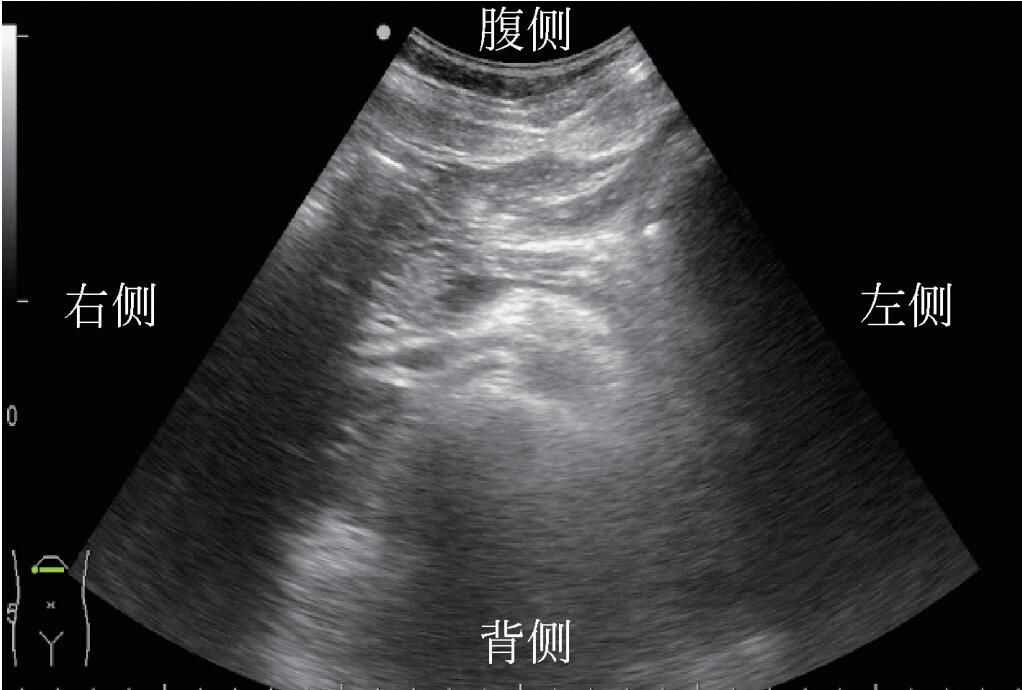

2)探头垂直于患者身体长轴90°扫查时为横向或轴向切面。若探头标记朝向患者右侧。则在有标记的屏幕侧的结构为患者身体右侧结构(图6)。

图6探头位置与声像对应关系(横向)